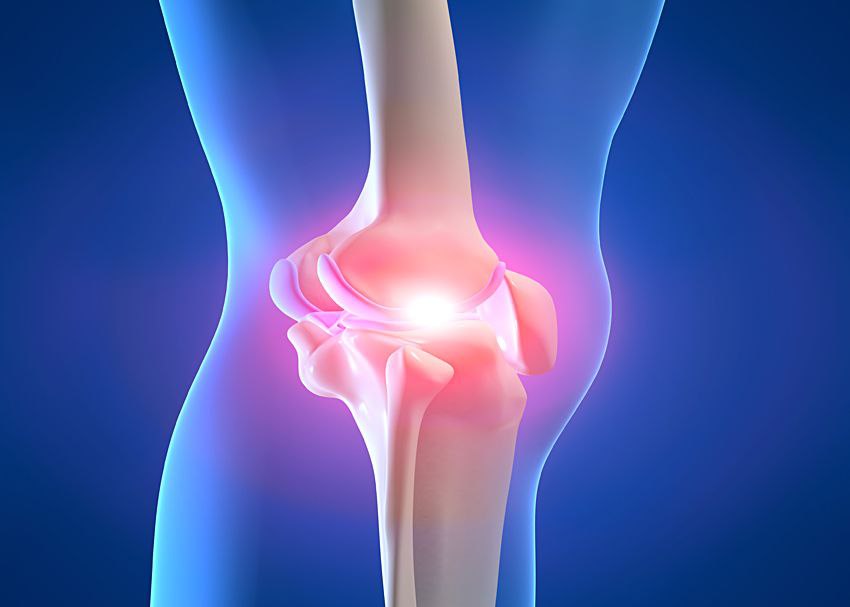

Анатомические рисунки суставов человека